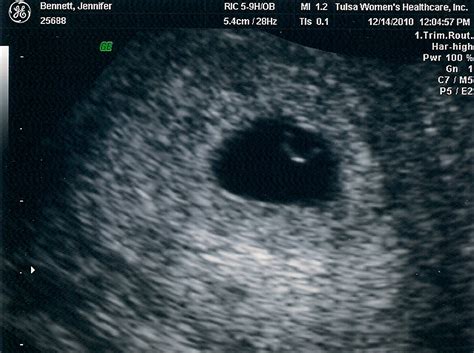

Ultrasound pics! - Page 5 — The Bump from us.v-cdn.net Ultrasound appearances of a pregnancy at 5 weeks gestation. Ultrasound 19 weeks 2 days pregnancy my sweet baby. I hadn't even had a chance to see my own dr. Prenatal ultrasound at 12 weeks. If your first ultrasound is earlier than seven weeks, the baby is often so small that it's hard to see with a traditional abdominal ultrasound. Ultrasounds performed during the first trimester can predict the baby's due date within 3 to 5 days. Now you're eight weeks pregnant, your baby is called an embryo. So now you know what to expect, but what exactly though ultrasounds are regarded as safe to mama and her baby, experts say, like any medical procedure, it bottom line:

Embryo to Fetus? from uniqueultrasound.com She is 2.55 cm long and has a heart rate of 164 beats per minute. The lower limbs are now held flexed at the hip and knee joints, and the legs may be crossed. This generally includes listening to baby's heartbeat, checking for physical abnormalities, looking at organ structure. 5 weeks 3 days vaginal ultrasound. You need to get another ultrasound and you need to v. Upload, livestream, and create your own videos, all in hd. Many women have ultrasounds every day, with no known effects. At 5 weeks, your embryo is too small to see yet, but the gestational sac may be visible on an ultrasound. look at a calendar, find the day your last period started, and count 280 days or 40 weeks forward.